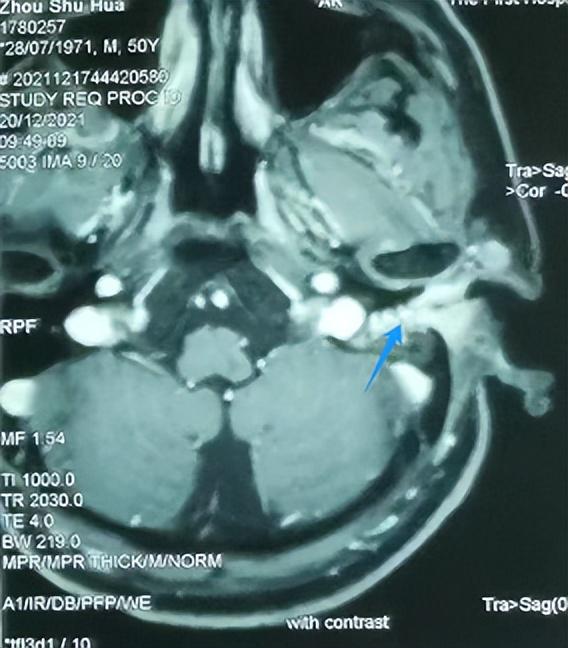

颞骨MRI:左外耳道肿物(蓝色为肿瘤)